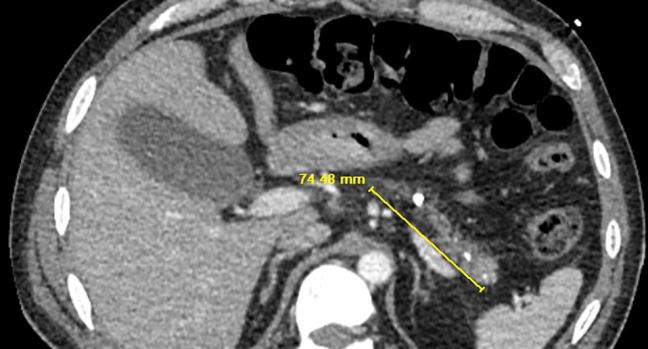

Folge des stetenAlkoholabusus: Atrophiertes Pankreas mit vielen Parenchymverkalkungen.

© Otero-Colón J et al. Cureus 2023; doi: 10.7759/cureus.38760